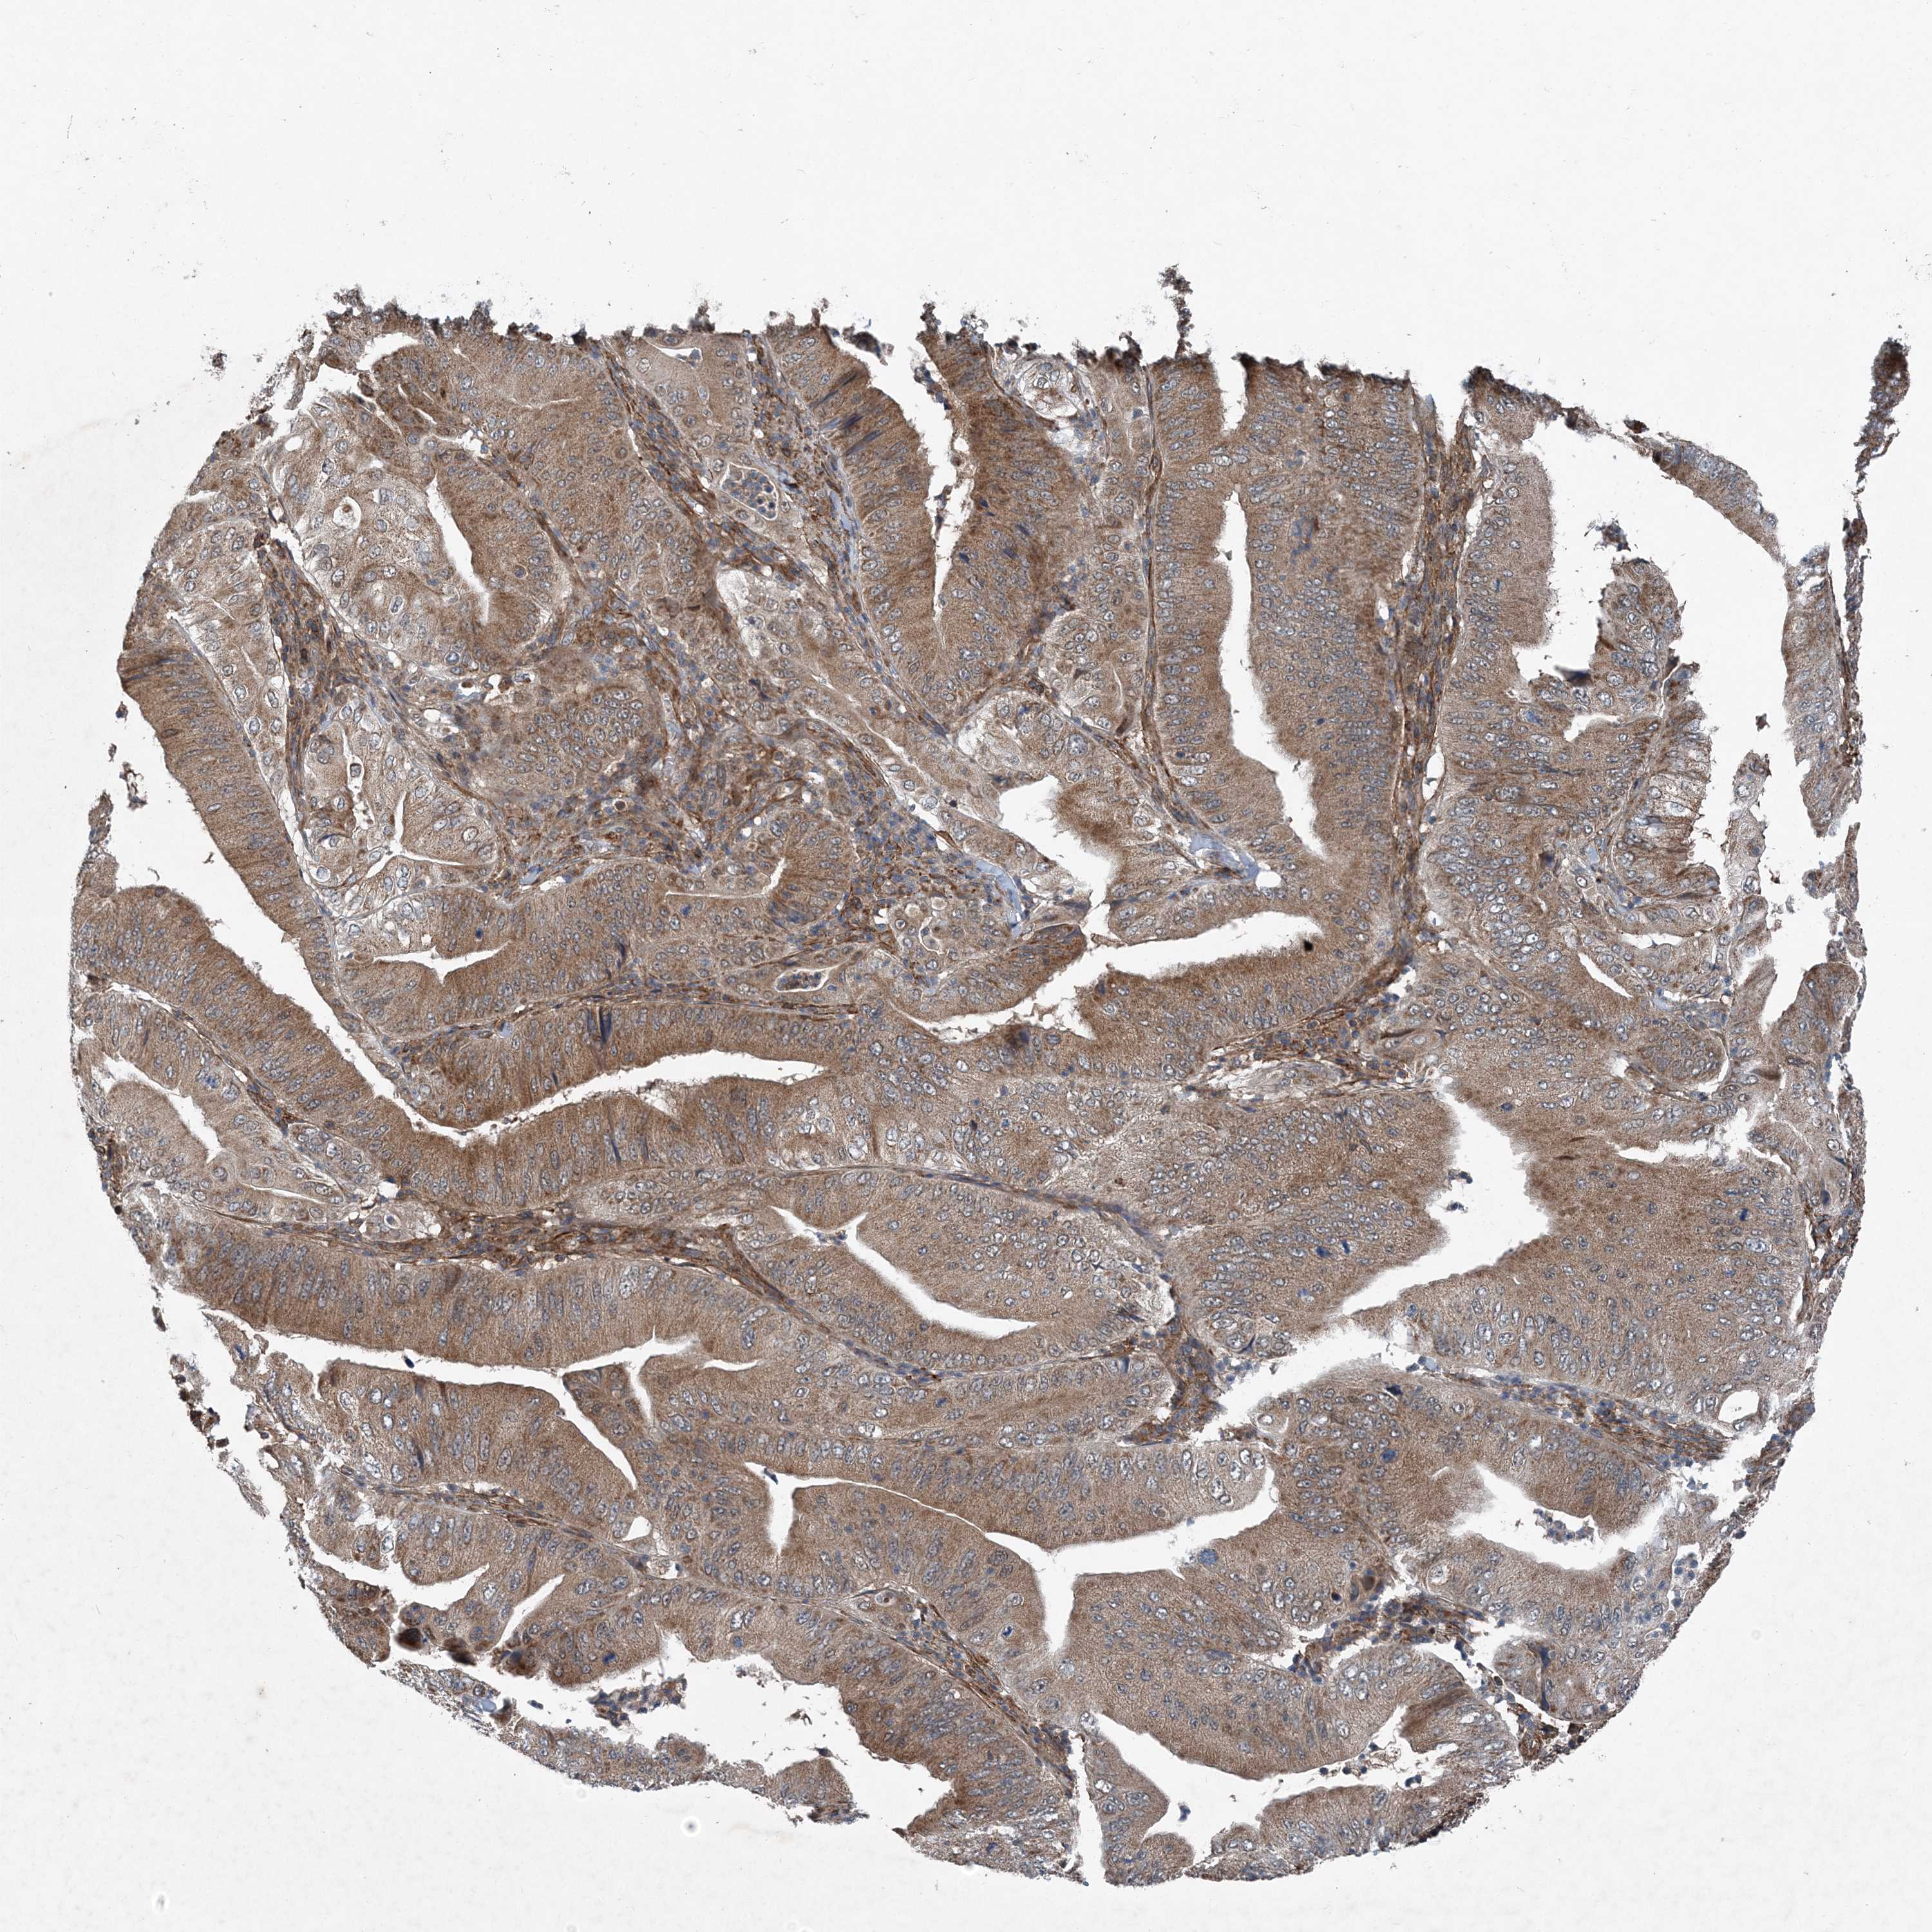

PANCREATIC CANCER - Protein expressioni

A mouse-over function shows sample information and annotation data. Click on an image to view it in a full screen mode. Samples can be filtered based on level of antibody staining by selecting one or several of the following categories: high, medium, low and not detected. The assay and annotation is described here.

Note that samples used for immunohistochemistry by the Human Protein Atlas do not correspond to samples in the TCGA dataset.

Antibody stainingi

Antibody staining in the annotated cell types in the current human tissue is reported as not detected, low, medium, or high, based on conventional immunohistochemistry profiling in selected tissues. This score is based on the combination of the staining intensity and fraction of stained cells.

Each image is clickable and will lead to virtual microscopy that enables deeper exploration of all samples and also displays staining intensity scores, fraction scores and subcellular localization as well as patient and tissue information for each sample.

Antibody HPA035933

Staining

High

Medium

Low

Not detected

Intensity

Strong

Moderate

Weak

Negative

Quantity

>75%

75%-25%

<25%

None

Location

Nuclear

Cytoplasmic/membranous

Cytoplasmic/membranous,nuclear

Adenocarcinoma, NOS